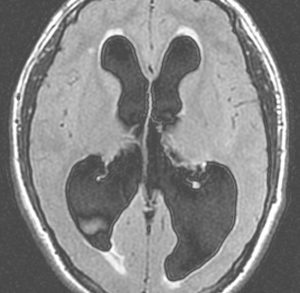

高度の閉塞性水頭症です。このくらいになるといつ意識がなくなっても,呼吸が止まってしまってもおかしくありません。ですから,緊急手術をします。ドレナージ,シャント術,第3脳室開窓術などです。原因となっている脳腫瘍を取り除くことで解決することもあります。